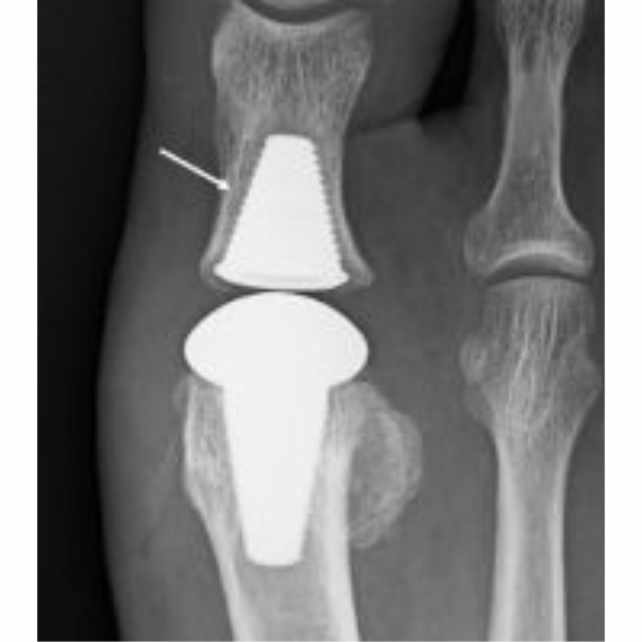

Radiografía de Implante completo en paciente con Hallux Rigidux

Dependiendo de estos factores se determinará si se realiza una artrodesis (fusión de la articulación), artroplastias o se opta por la recuperación de la movilidad de la articulación mediante hemiimplantes o implantes completos de la primera articulación metatarso falángica, según se considere lo más indicado en cada caso.

Técnica con implante completo